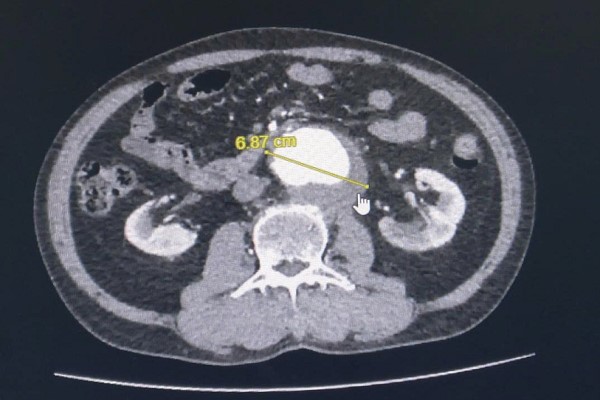

Giải pháp nào cho bệnh nhân phình động mạch ‘bất lực’ trong việc đặt stent?

Thứ Ba, ngày 30/09/2025 09:58Khi nhân bị phình động mạch chủ bụng, đe dọa đến tính mạng nhưng không thể mổ mở và cũng không thể đặt stent, bác sĩ phải làm gì để cứu họ trong tình trạng “ngàn cân treo sợi tóc” này ? ...